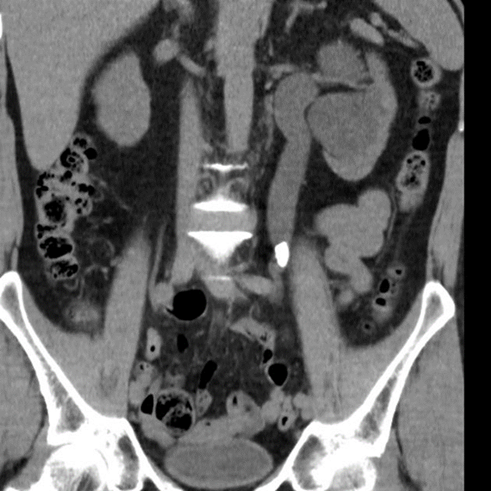

Akut handläggning

• Splint (dubbel JJ-stent) alt Nefrostomi. Vid avstängd pyelit

o Nefrostomi via flank UL-lett, urin ut i påse (förstaval då vi vet att denna funkar, vi får urin ut direkt liksom)

o Splint (bilden) via urinröret till blåsen, sedan till uretärostiet, guidevajer till njure och sedan slang, när vajern dras ut krullar slangen till sig i njure (och även kringla i blåsan) och urin leds ut via denna slang

Vad visar bilden?